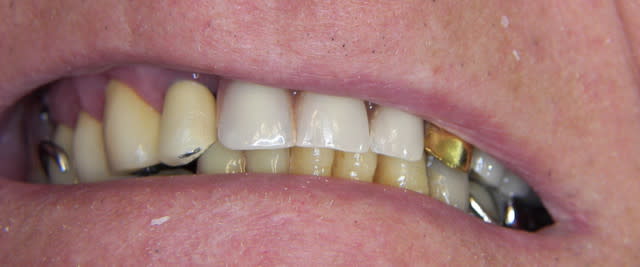

et maintenant

Img 1187 scxhsv - Eugenol

Img 1188 r4hkjo - Eugenol

Img 1189 fazbfe - Eugenol